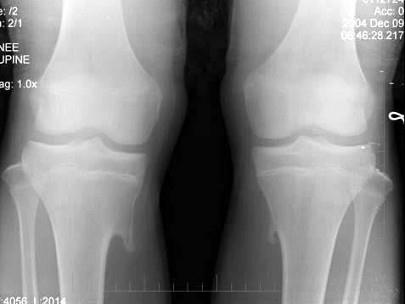

问题 男,14岁,偶然发现双膝部肿块1天,双膝关节摄片如图,最可能的诊断是?(?)

选项 A.骨瘤 B.骨软骨瘤 C.局限性骨皮质增厚 D.软骨肉瘤 E.以上均不正确

答案 B